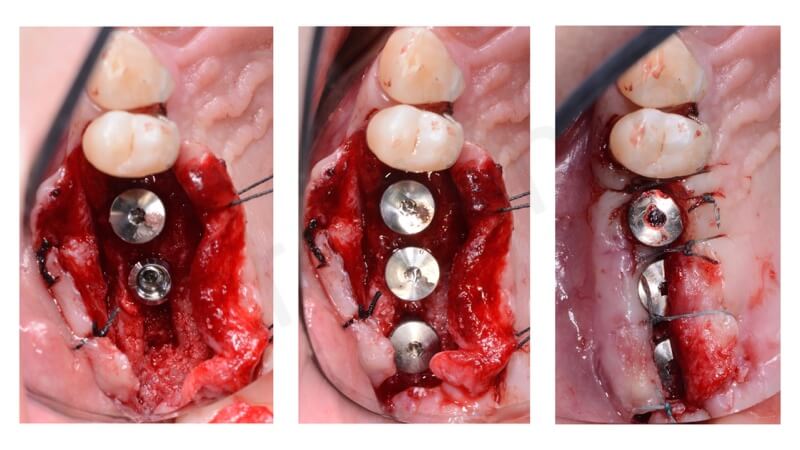

As first step, a linear crestal window is opened by means of a sonic handpiece. After the Schneiderian membrane detachment, a BioOss Collagen graft is inserted.

In this case 3 Straumann Tissue Level Tapered Effect Implants have been placed.

sinus lift crestal approach Bio.Oss Collagen graft

Implant placement